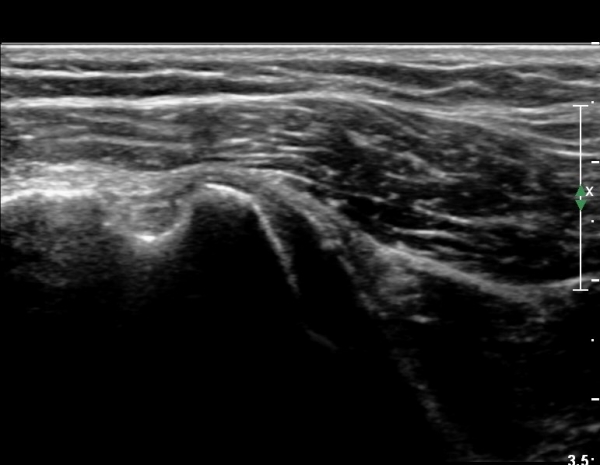

ÃÊÀ½ÆÄ °Ë»ç

´ë°áÀý°ú °ßºÀÇϺο¡ ¹æ»ç¼± Åõ°ú¼º °¨¼Ò(sclerosis)°¡ °üÂûµÈ´Ù(÷ºÎÆÄÀÏ).